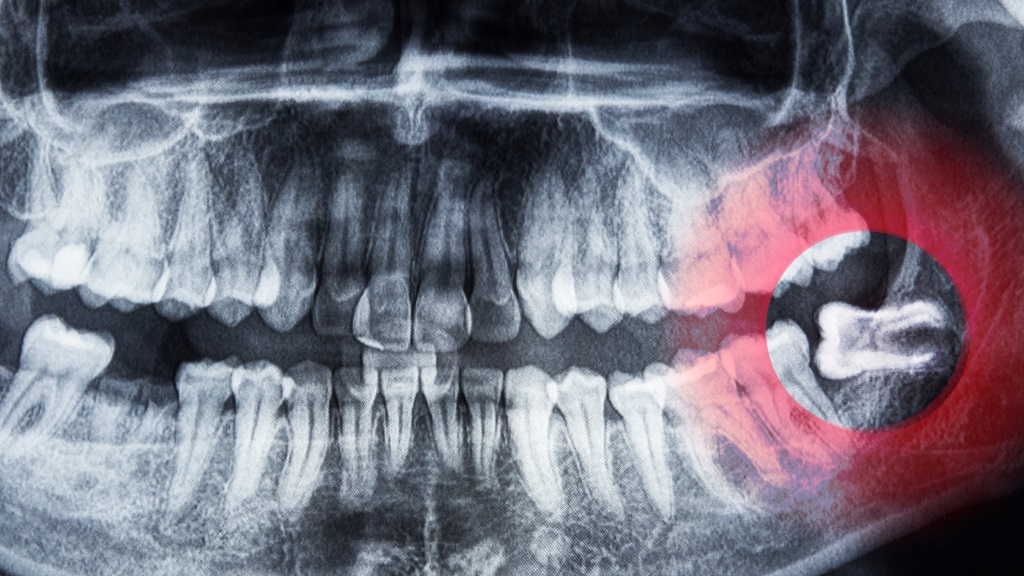

The third molars, popularly called wisdom teeth, are frequently taken out because they typically lack the room needed to emerge correctly, resulting in impaction. Issues associated with wisdom teeth include:

- Impaction – When wisdom teeth do not fully emerge from the gums, they can become trapped and cause pain, swelling, or infection.

Our dentist in Surrey will carry out an in-depth assessment, utilizing X-rays to understand the status of the tooth and the adjacent bone.